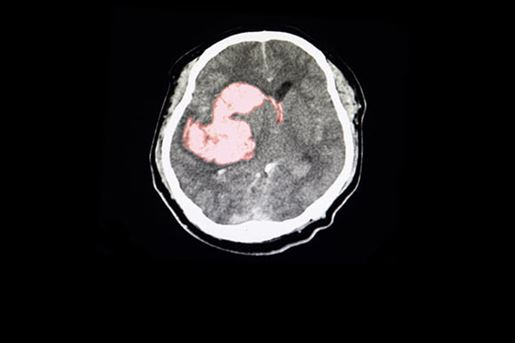

- The current performance measures are based on the 2022 AHA/ASA Management of Spontaneous Intracerebral hemorrhage (ICH) guideline.

- The continual improvement of healthcare systems for ICH patients is important given the high mortality and morbidity of ICH.